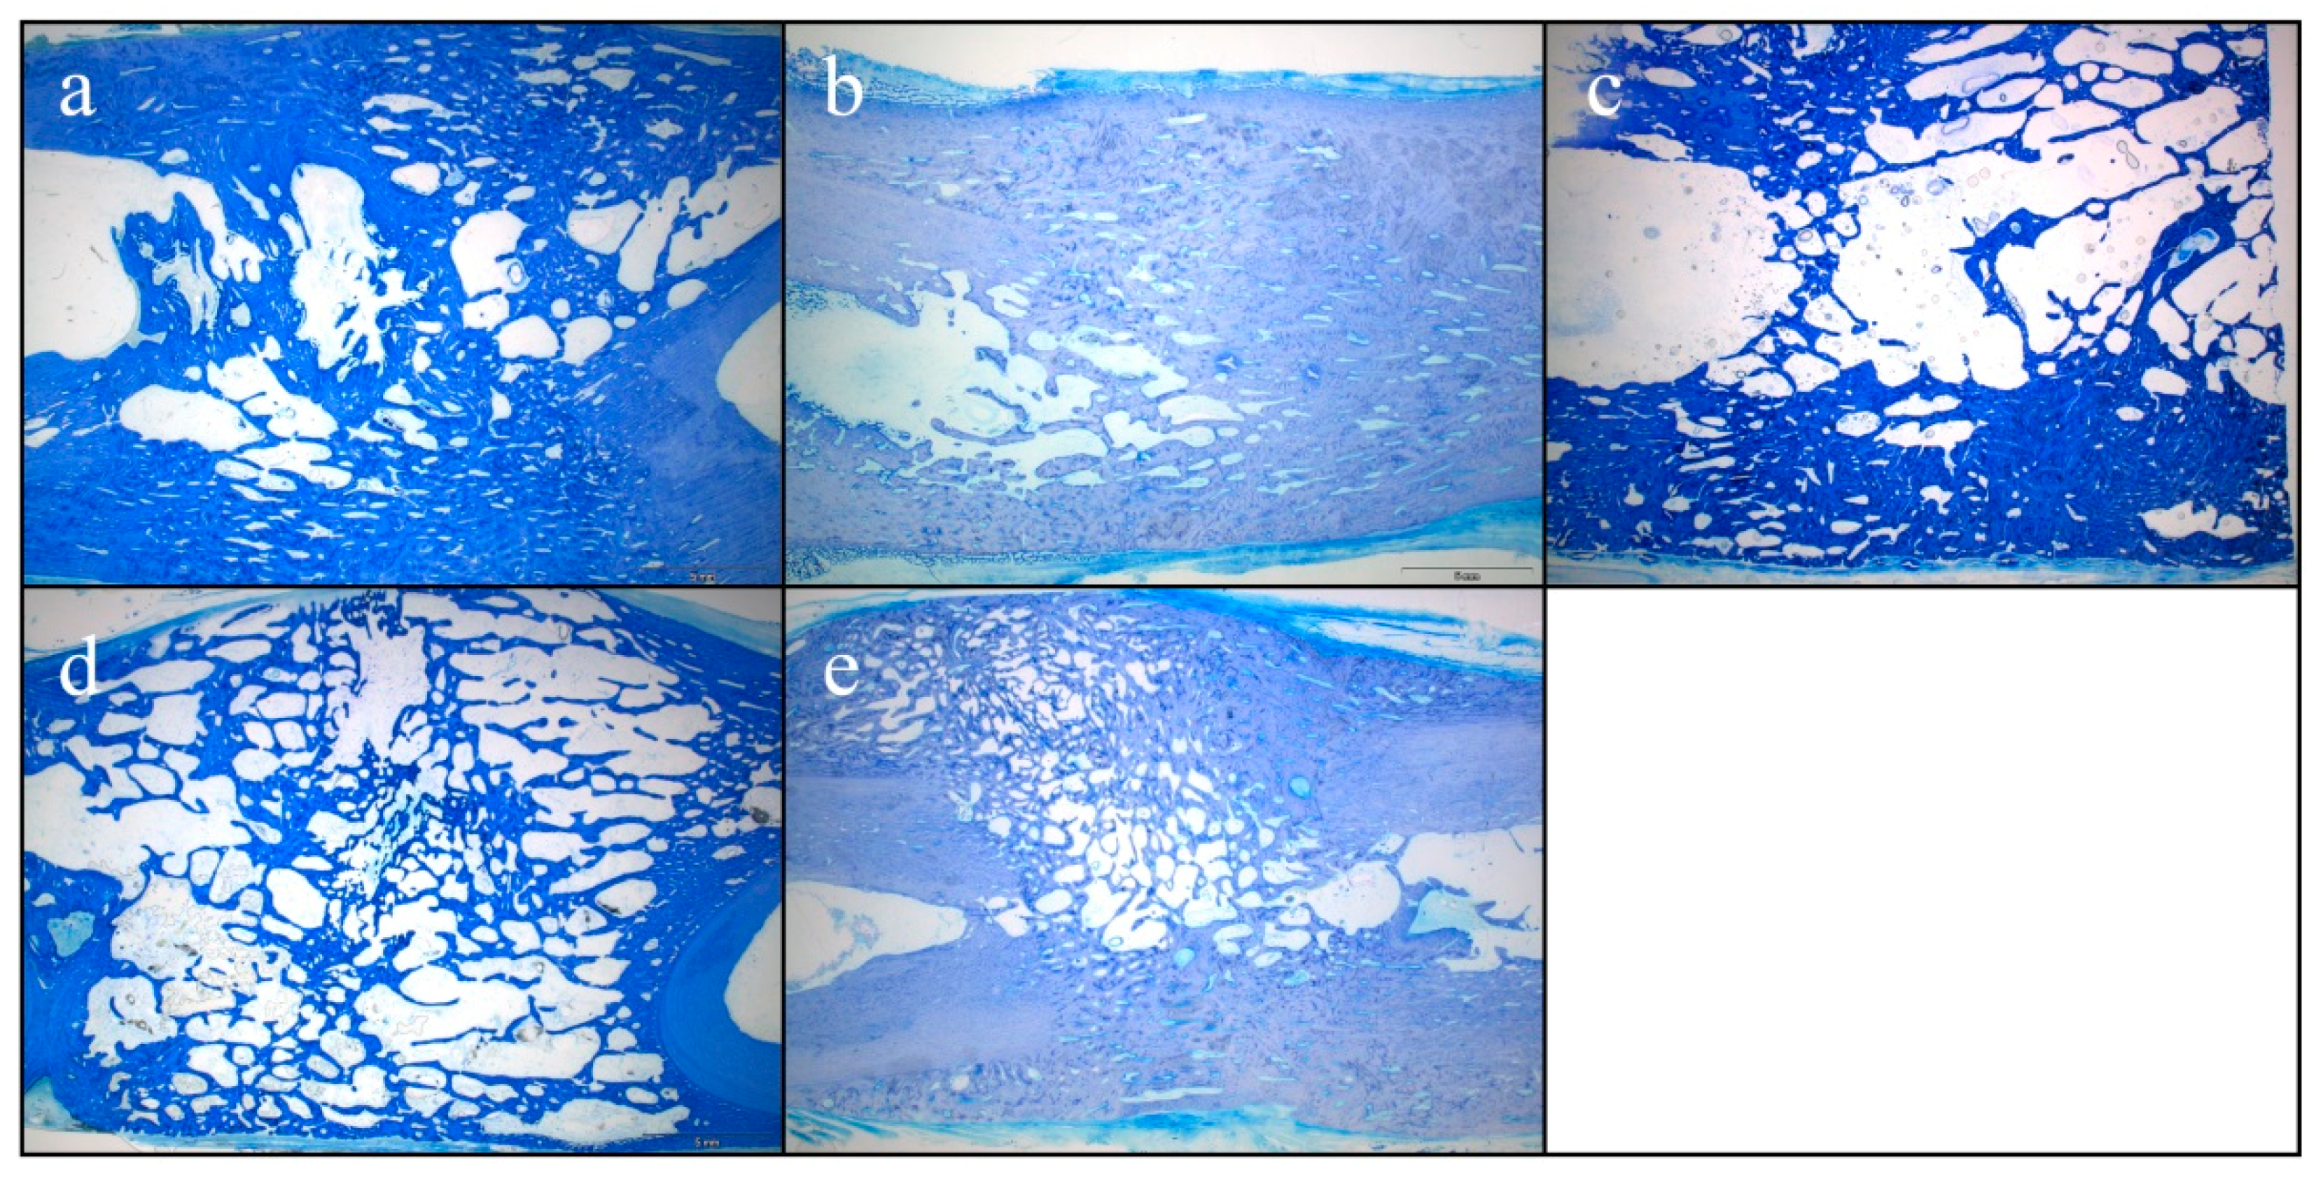

2.7. Histological Results of Bone Formation

Representative histological sections of the healed bone defects are displayed in Figure 5. While mature bone was observed throughout the defect with lamellar aspect and small lacunae in the test group (Figure 5a,d) and in the control group (Figure 5b,e), immature bone was observed with larger lacunae and disorganized mineralized matrix in the HA group (Figure 5c). The distance between the original bone fragments varied from 16.8 to 22.7 mm, resulting in a measurement area of the former tibial bone defect of 298 to 457 mm2 (Table 1). Histomorphometric analysis revealed that the area of newly formed bone was largest in the control group with 82.5 ± 5.5% compared to 59.2 ± 13.0% in the test group and 48.6 ± 2.9% in the HA group. Bone regeneration was superior in the control group without any bovine hydroxyapatite (Table 1).

Figure 5.

Toluidine blue staining of the former tibial bone defect area: (a,d) test group; (b,e) control group; (c) HA-group.